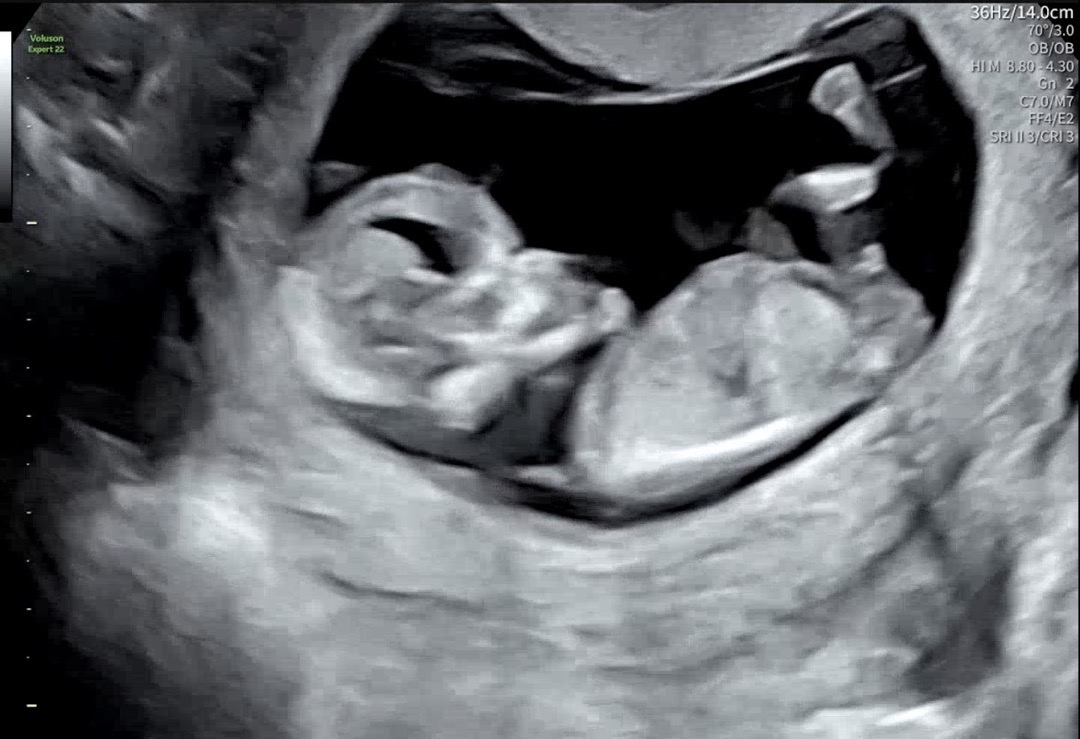

오늘 12주차 정밀초음파 보고왔는데 한번식 투표 부탁드려요!!ㅠㅠ🫶🏻